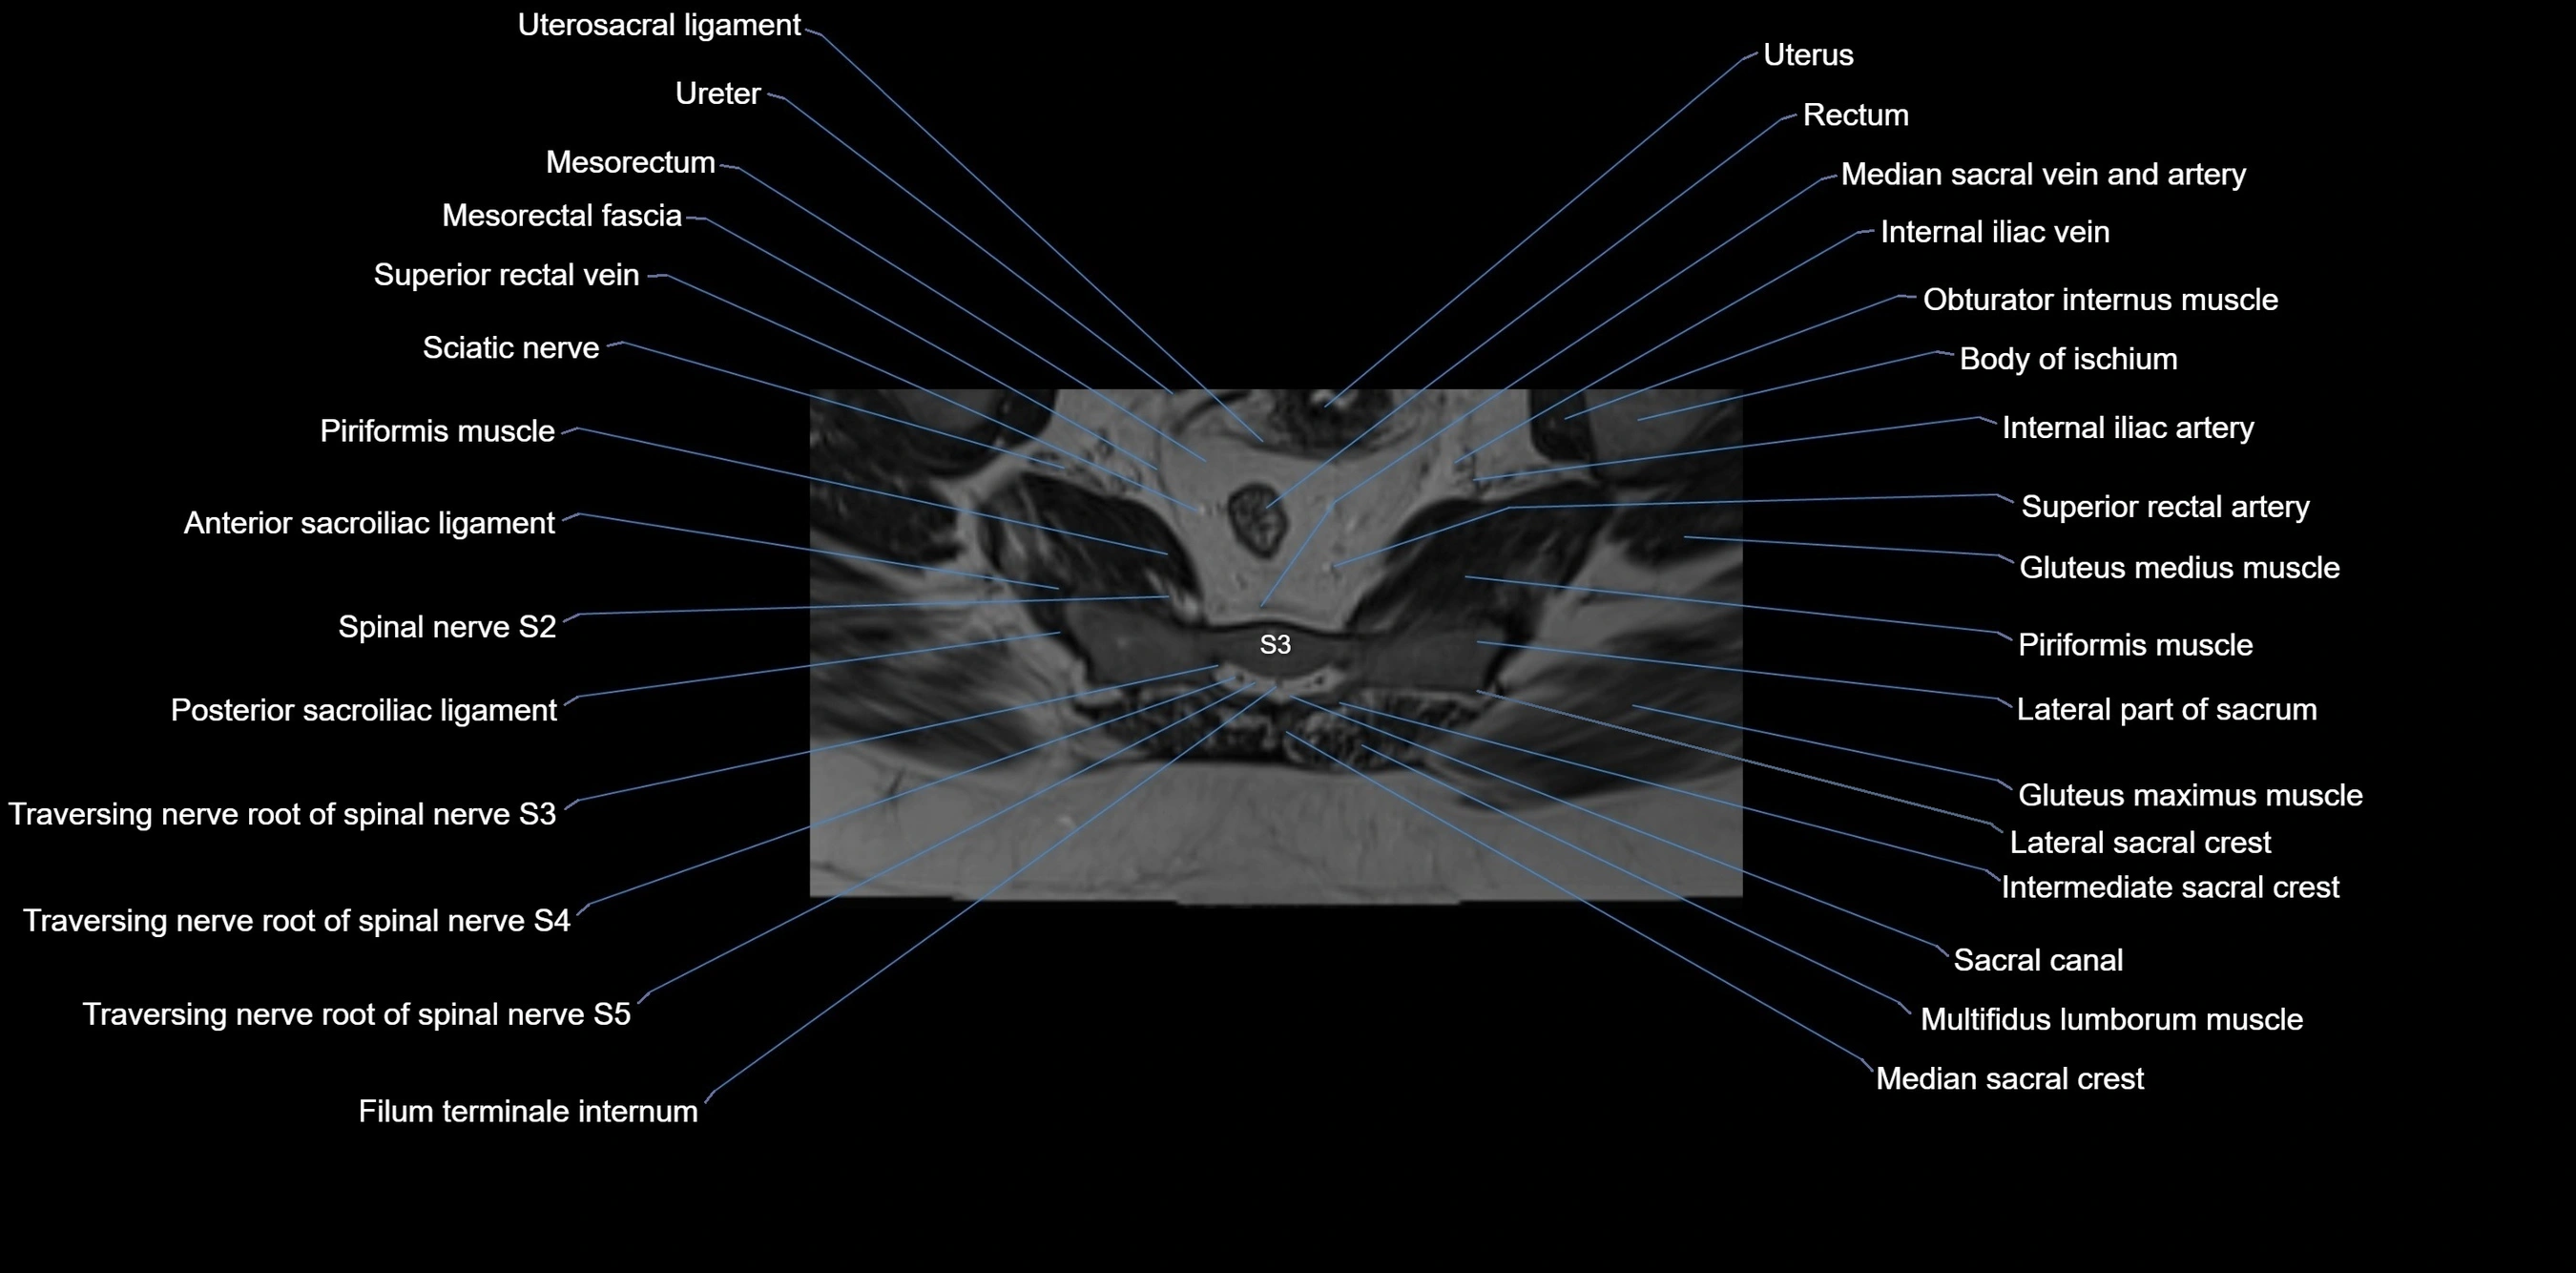

CT image

image